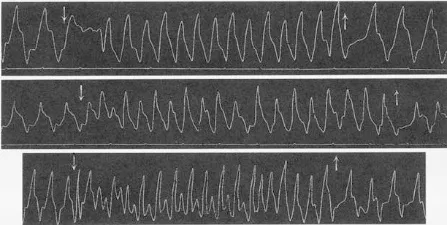

18世纪末期,心脏外部电刺激的治疗方式首次被记录在伦敦皇家人类学会。19世纪末期,Hugo Von Ziemssen切除了前来就诊的女病人的胸部肿瘤,从而使心脏暴露。他发现电流能产生心室活动,通过改变电流还能改变心律。

(图:电流实验图)